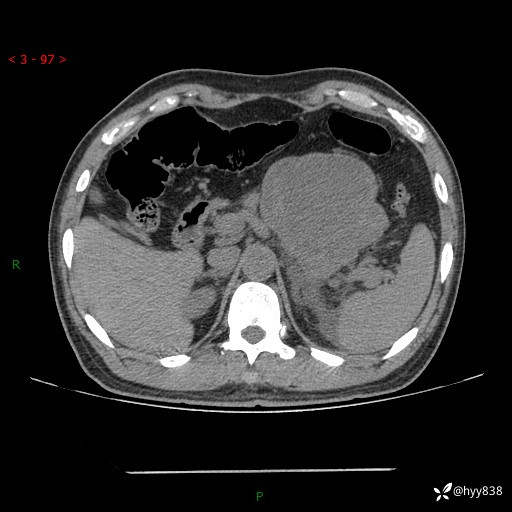

病例39岁/女,左侧腰痛入院。腹腔囊实性肿块,定位、定性---结果公布~

性别:男

年龄:39岁

简要病史:左侧腰痛待查,CT发现腹腔占位

腹部CT平扫+增强